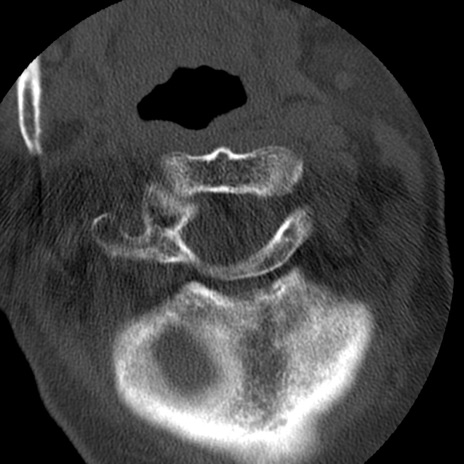

症例50 頚椎CT(横断像)

頚椎CT